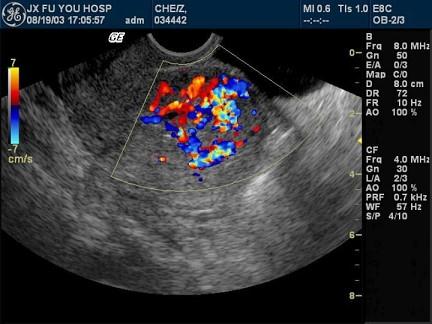

问题 女性,36岁,行常规超声妇科体检。声像图表现如图。血HCG为2258μg/ml。最可能的诊断是?(?)

选项 A.绒癌 B.子宫腺肌瘤 C.早期妊娠 D.子宫肌瘤 E.良性葡萄胎

答案 A